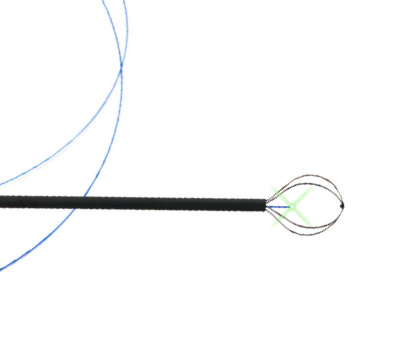

Excellent memory and flexibility

Minimal trauma and Bleeding

With tuohy borst connected, allowing 272μm Fiber to be introduced

| Reference | Description | Ø (Fr) | Wire | Working Length (cm) | Basket Ø (mm) | Basket Length (mm) |

|---|---|---|---|---|---|---|

| ROKP1001ST | PerkX Coaxial PCNL Stone Extractor for Rocamed Laser Fiber max 272μm | 10 | 4 | 38 | 20 | 17.5 |